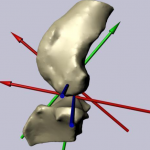

Εκτιμηση Δυσπλασιων αγκωνος MCD,FCP,UAP

Απαιτουνται ειδικες πολλαπλες ληψεις και μετρησεις ειδικων σημειων.Πολλες φορες χρειαζεται η εκτιμηση με CT και σε αρκετες περιπτωσεις,ενω μπορει να υπαρχει ηδη συμπτωματολογια(χωλοτητα),το προβλημα δεν αποκαλυπτεται.